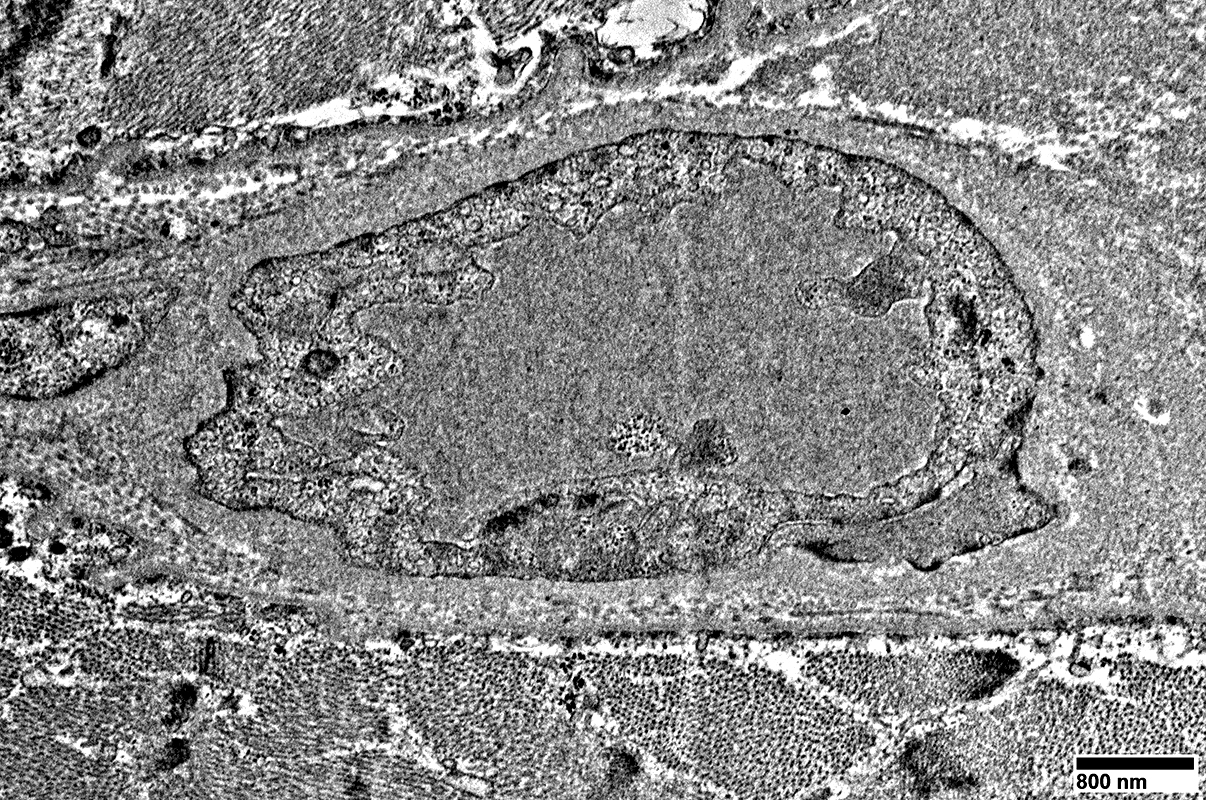

MELAS: Mitochondrial Ultrastructure

From: R Schmidt

Endomysial vessels with

Large endothelial cells with many vesicles

No lumen

Many smooth muscle cells in wall, some with mitochondrial proliferation (Arrow)

Thick wall

Large endothelial cell with many vesicles

Scattered smooth muscle cells in wall

Endomysial capillaries

Endothelial cells with many vesicles

Large size